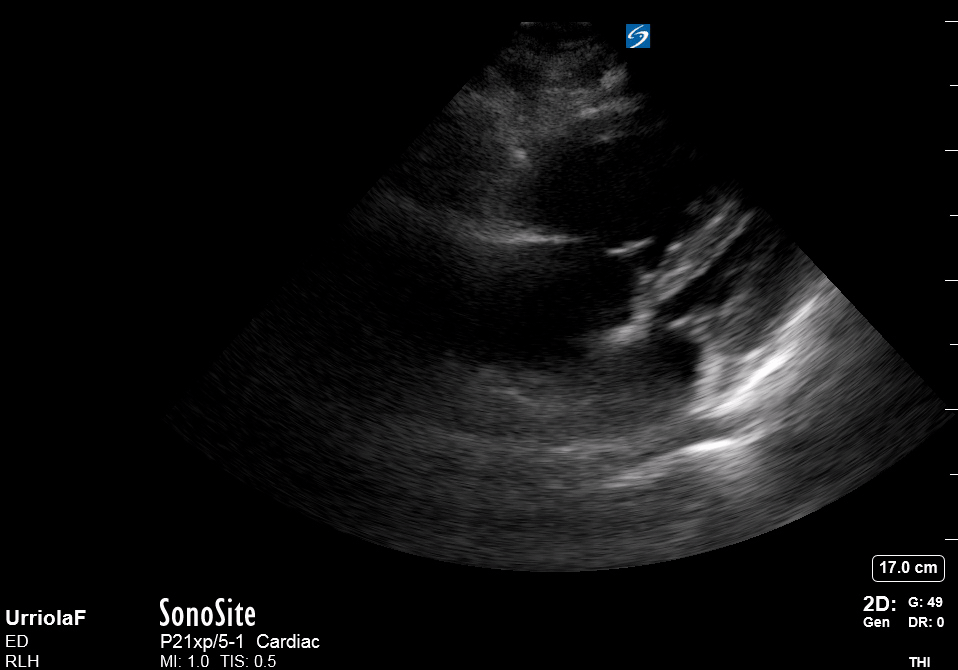

Equality: is the RV dilated or significantly impaired?

Normally, the RV is a low-pressure, thin-walled, high-compliance chamber that wraps anteriorly around the muscular, cone-shaped LV. The normal RV : LV diameter ratio is 0.6 : 1.

When the pulmonary artery pressure rises, the RV will dilate, altering the normal RV:LV ratio. Although sacrificing sensitivity, the use of equality (1:1 ratio) as a cutoff can achieve a specific estimation of RV strain. If imaged correctly by a trained operator, the presence of an RV:LV ratio > 1 is highly specific for RV strain.

RV dilation can be acute, chronic, or acute-on-chronic. However, in patients presenting with undifferentiated chest pain, shortness of breath, hypotension or syncope, the presence of any RV dilation should raise suspicion for acute pulmonary embolism (PE). Furthermore, in a patient in shock, the presence of RV strain may signal the need for aggressive therapy – emergency thrombolysis.

THE VIEWS

The A4C view provides an accurate chamber size comparison. However, achieving a proper A4C view (avoiding foreshortening or ballooning, and visualising the four chambers with a vertically oriented interventricular septum) can be a challenging exercise of image acquisition. Additionally, the PSAX view at the level of the papillary muscles shows both LV and RV side by side and is useful to assess function and size. When RV pressure is high, the septum will be pushed and flattened towards the LV, resulting in the characteristic “D-shaped” LV or “D sign”.

PITFALLS

When comparing size, beware of correct image acquisition, as oblique planes lead to misinterpreting the RV:LV ratio. For apical views be sure to slide the probe sufficiently laterally on the chest wall so that it lies over the true apex. Also, be sure to obtain a real horizontal plane, avoiding foreshortening (ballooning). For the PLAX view it is useful to fan through the heart’s long axis, making sure that LV visualization is maximized relative to the RV. Furthermore, an understanding of probe placement and marker orientation conventions is fundamental. If inadvertently scanning in reverse orientation, the normally larger LV could be mistaken for an abnormally enlarged RV.